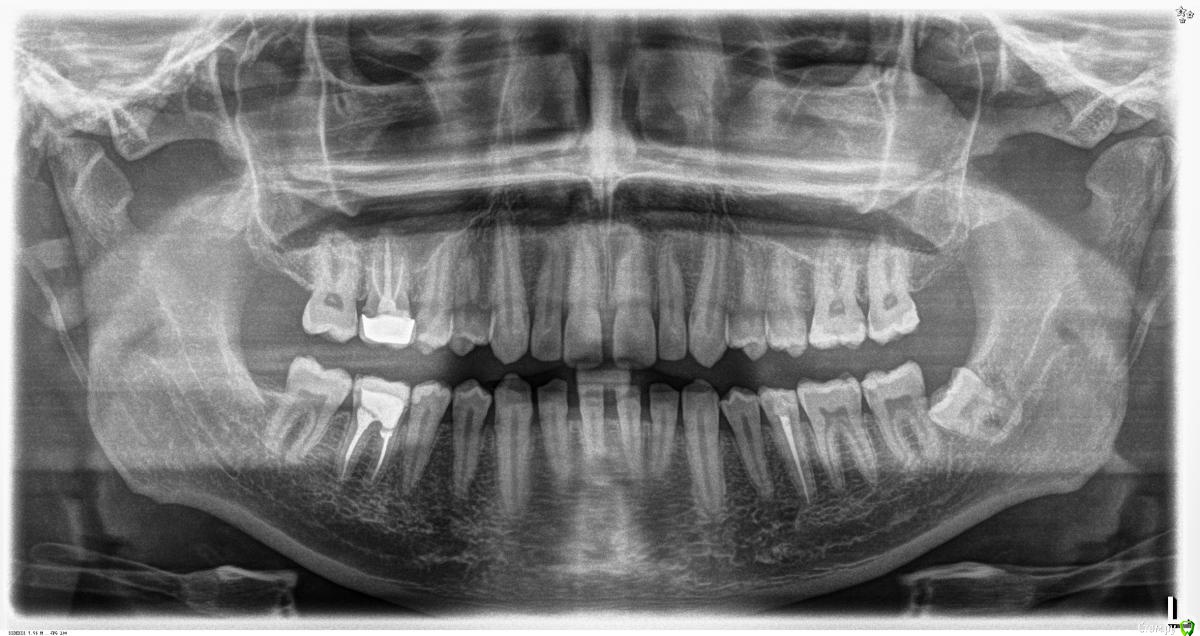

aleksvander Опубликовано 29 декабря, 2016 Поделиться Опубликовано 29 декабря, 2016 (изменено) Доброе время суток жители форума. Давно мучаюсь с 35ым зубом, еще очень давно у него отломился кусочек и с внутреней стороны стенки он был слегка острым, прошло пару лет и там образовался поверхностный кариес. Пролечил но проблему это никак не решило, из за которой я собственно и обратился. А проблема заключалось в следующем, что зуб (особенно если что то жевать и при том правой стороной челюсти хотя зуб слева), иногда верхний зуб задевал переднею стенку и возникала боль. Я обратился повторно к врачу, тот в свою очередь решил мне по гарантии пере лечить зуб кардинально! путем удаления нерва и пломбировкой канала с помощью какой то ?резины? которую в последствии поджигали. Во время пломбирования (на завершающей стадии) возникала резкая боль под зубом. Что мне показалось странным. Прошло 3 - 4 месяца, боль периодически возникала как до лечения. Но вот совсем не давно, зуб стал болеть постоянно и плюс к тому же от любого прикосновения к передней стенки появилась некоторая чувствительность. Эпизодически стали появляться резкая блуждающая боль. Я начал сомневаться, а в зубе ли дело? Но при очередном неудачном жевании мои сомнения развеялись, когда верхняя челюсть слегка ушла в сторону и надавила на переднюю стенку зуба, появилась резка боль. Сходил к врачу сделали повторный снимок... ничего, только вот длина пломбированного канала мне показалась выходящая за пределы корня зуба... это допустимо? Так как врач мне ничего конкретного не ответил, я настоял на том что бы сделать более подробный снимок, в итоге меня отправили на 3д грамму или как там ее называют. Экспертны подскажите пожалуйста что делать, к кому обращаться?На панорамном снимке я увидел что зуб мудрости у меня вылез не удачно, этим вопросом я займусь. Сразу как начнет работать городская хирургия, и не думаю что с этим может быть связано, т.к. проблема очень давняя и чаще всего возникает банально при жевании жвачки, при том что в другой части челюсти. Изменено 29 декабря, 2016 пользователем aleksvander 1 Ссылка на комментарий

aleksvander Опубликовано 29 декабря, 2016 Автор Поделиться Опубликовано 29 декабря, 2016 (изменено) Ссылку на исходный размер изображения прилагаю.https://yadi.sk/i/WcC9Iv0_35n7hL и еще... врач прописывал Азитрокс, ну увы никакого результата это не дало, кроме подскаженного желудка. Изменено 29 декабря, 2016 пользователем aleksvander 1 Ссылка на комментарий

shishok Опубликовано 29 декабря, 2016 Поделиться Опубликовано 29 декабря, 2016 Возможно вертикальный перелом(трещина).Нужен прицельный осмотр. Ссылка на комментарий

shishok Опубликовано 30 декабря, 2016 Поделиться Опубликовано 30 декабря, 2016 К сожалению,на фото и Рг-снимке трещину не увидеть.Нужен очный осмотр стоматолога(потрогать,постучать и т.д.). Ссылка на комментарий